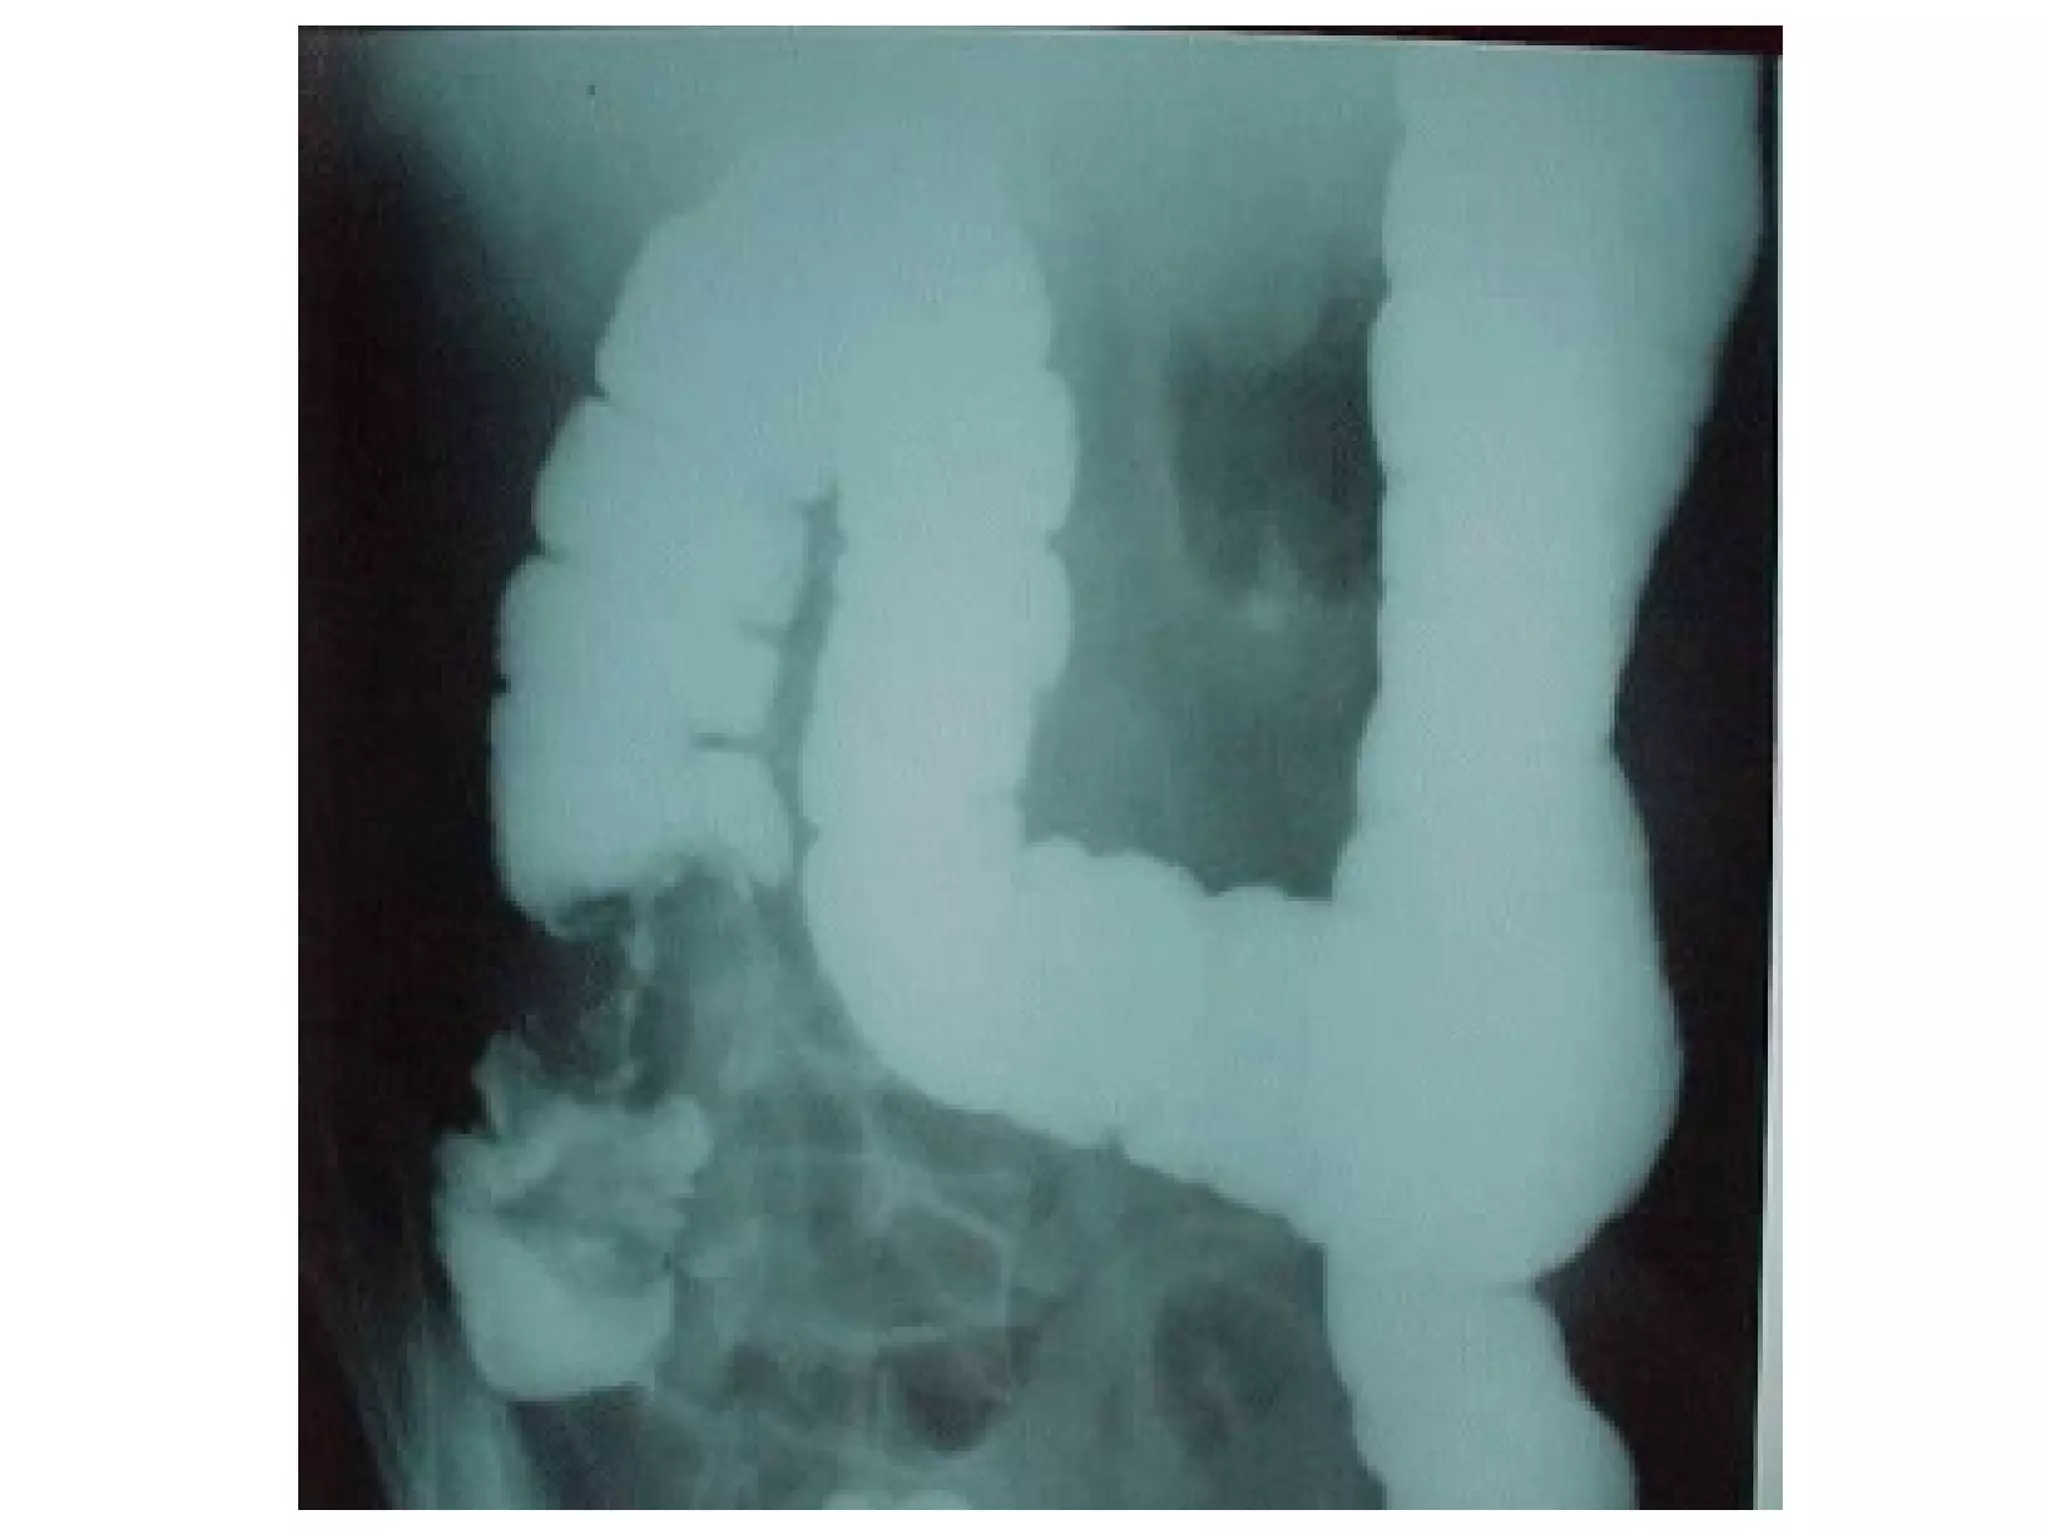

Barium enema- Ca colon Ix name? Barium enema Describe? Filling defect + shouldering (apple-core) Annular stricture (irregular) Dx? Ca colon S&S? Altered bowel habit (> rectosigmoid) LOW LOA anemia (> cecum)

Barium enema- Cacolon Ix name? Barium enema Describe? Filling defect + shouldering (apple-core) Annular stricture (irregular) Dx? Ca colon S&S? Altered bowel habit (> rectosigmoid) LOW LOA anemia (> cecum)